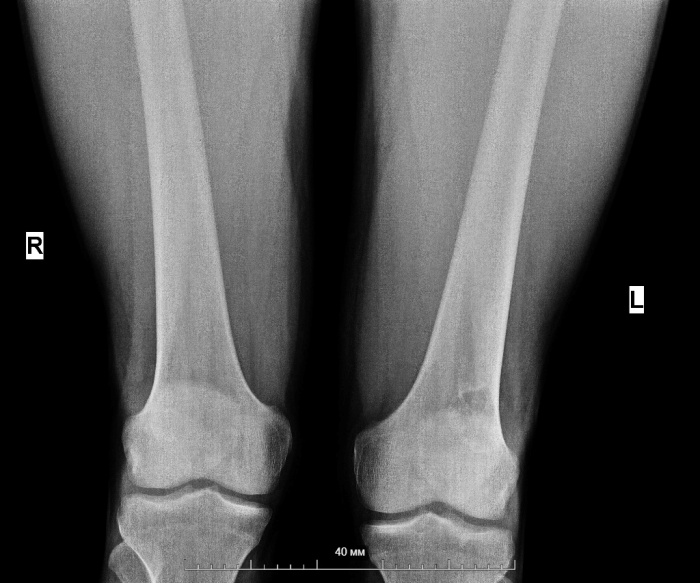

1. Рис. 1. Рентгенография коленного сустава. Участок деструкции кости по медиальной поверхности наружного мыщелка левой бедренной кости. Примечание: рисунок выполнен авторами | |

3. Рис. 3. СКТ коленного сустава. Зона реконструкции и ремоделирования в области ранее резецированного участка кости слева. Примечание: рисунок выполнен авторами | |